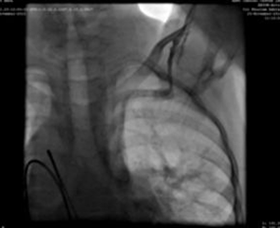

Nadi femoral dan arteri kanan diberi selubung radial 5F. Selama prosedur, kami menemukan vena cava (IVC) inferior untuk mengeringkan kelanjutan azygous menuju vena cava superior kanan dan kemudian Lacak melalui sinus koroner yang dildo di atrium kanan. Sebuah keputusan untuk menjalankan prosedur dari pembuluh darah internal kiri (dengan diakses 5F radial) dibuat.

Tusukan pembuluh darah jugler kiri, dan kateter angiografi 5F, menunjukkan pembuluh lengan atas-jalur koneksi atrium kanan vena cava superior.

Kami menggunakan selubung pengiriman 9F, yang canggih dan ditempatkan di aorta turun di atas guidewire super kaku. MemoPartTM cone shape PDA occluder 14/12 mm, was attached to the delivery cable and progressed across the delivery sheath. The placement of the occlude was proper with no residual flow.